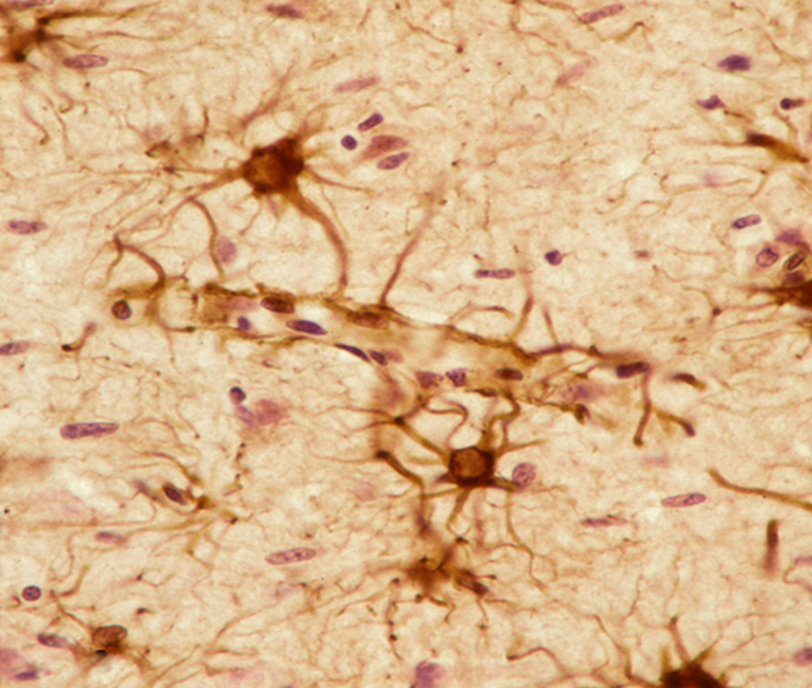

An important marker for labeling glial tumors

glial fibrillary acidic protein (GFAP), an intermediate filament protein

Astrocytes

GFAP stain

Glioma but make sure its not a met by staining with GFAP

Glioma stained with GFAP